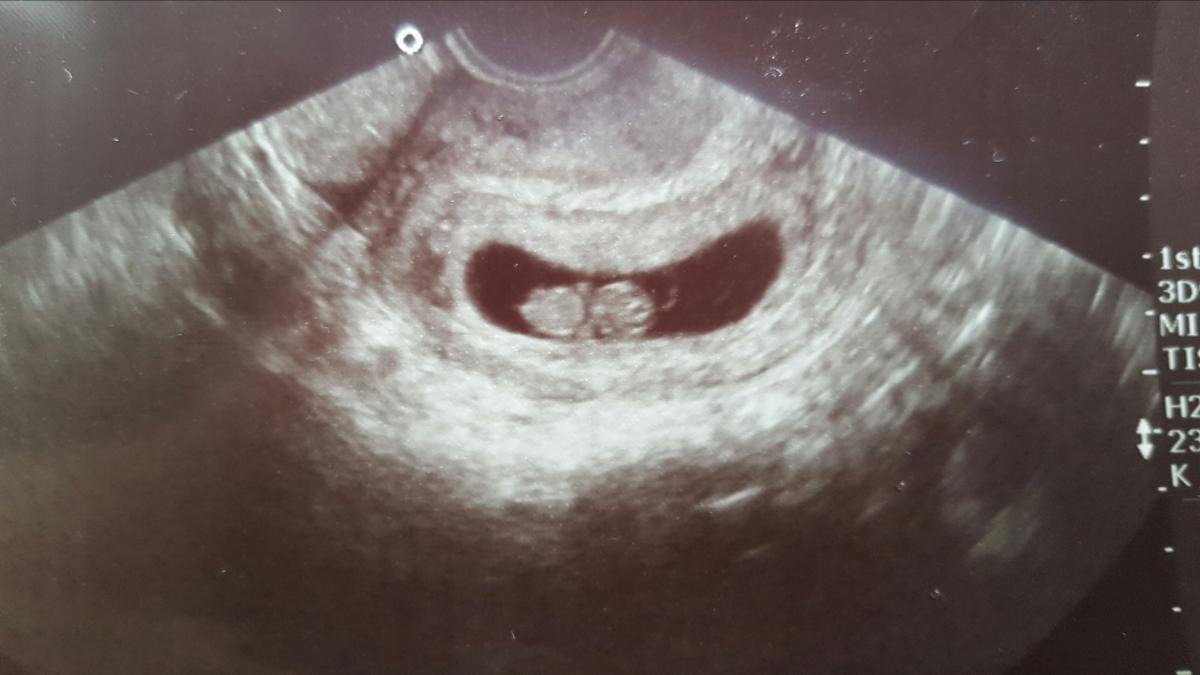

Az egypetéjű ikreknek több típusa van attól függően hogy mikor válik ketté a zigóta. A zigóta kettéhasadés a szétvált sejtekből két teljes értékű önálló egyed fejlődik legkorábbi szétválás két sejtes állapotban 60 órával a fogamzás után. Ezek sebészeti elválasztása valamely csecsemő halálával is járhat. Rendkívül hasznos dolog ha az embernek ikertestvére van és nem csak azért mert biztosan akad valaki akivel közösen tudja ünnepelni a születésnapját.

Embereknél az egypetéjű ikrek esetében a petesejt első 14 napjában bekövetkezik a szétválás ez után már nem. Azért mert az egypetéjű ikrek mint az elnevezés is utal rá ugyanabból a megtermékenyített petesejtből fejlődnek ki csak kettéválnak. Napon történik akkor a magzatok méhlepénye közös de külön burokban növekszenek mono di ikrek. Az egyikük sienna olyan betegségben szenvedett ami törpenövést okozott.